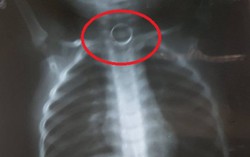

Tiền xu mắc trong thực quản bé trai 5 tuổi

Phòng & chữa bệnh 15:10 18/04/2017Trong lúc nô đùa, bé Phạm Bảo Nam, 5 tuổi, ở xã Tân Trào, huyện Sơn Dương, tỉnh Tuyên Quang, đã nuốt 1 đồng xu vào miệng. May mắn gia đình phát hiện đưa bé đi cấp cứu kịp thời.